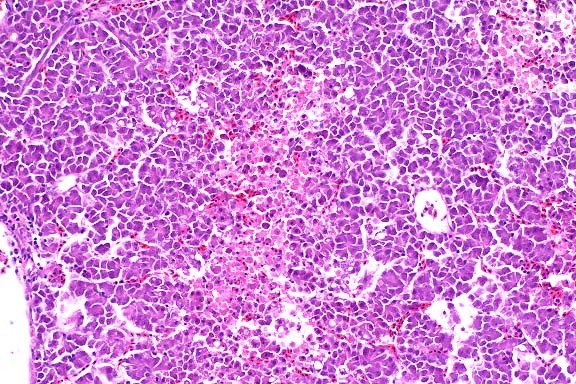

- The lung has multiple, discrete, subpleural granulomas which

each contain a single immature cestode that lacks a bladder wall.

The cestode larvae are nonsegmented and contain an invaginated

scolex. Occasional sections of the larvae show the presence of

suckers in the invaginated canal. Larvae have multiple small

lightly basophilic calcareous corpuscles. The reaction is characterized

by fibrous septal thickening, type II pneumocyte hyperplasia

and a mix of inflammatory cells consisting of eosinophils, macrophages,

plasma cells, and lymphocytes. A layer of degenerate inflammatory

cells lies adjacent to the cestodes. The pleura is thickened

by chronic pleuritis.

- Case 8-1 . Lung. The 2x view shows 3 profiles of cestode

larva surrounded by a dense inflammatory infiltrate forming a

granuloma adjacent to the pleura surface. Surrounding alveoli

have mild alveolar emphysema and thickened alveolar septa. At

40x, multiple calcarious corpuscles (blue bodies with clear halos)

are scattered within the mesenchyme of the larva. The tegument

has a thick eosinophilic, 15-20u, smooth surfaced cuticle. The

surrounding interstitium is fibrotic with moderate numbers of

infiltrating eosinophils and fewer macrophages and lymphocytes.